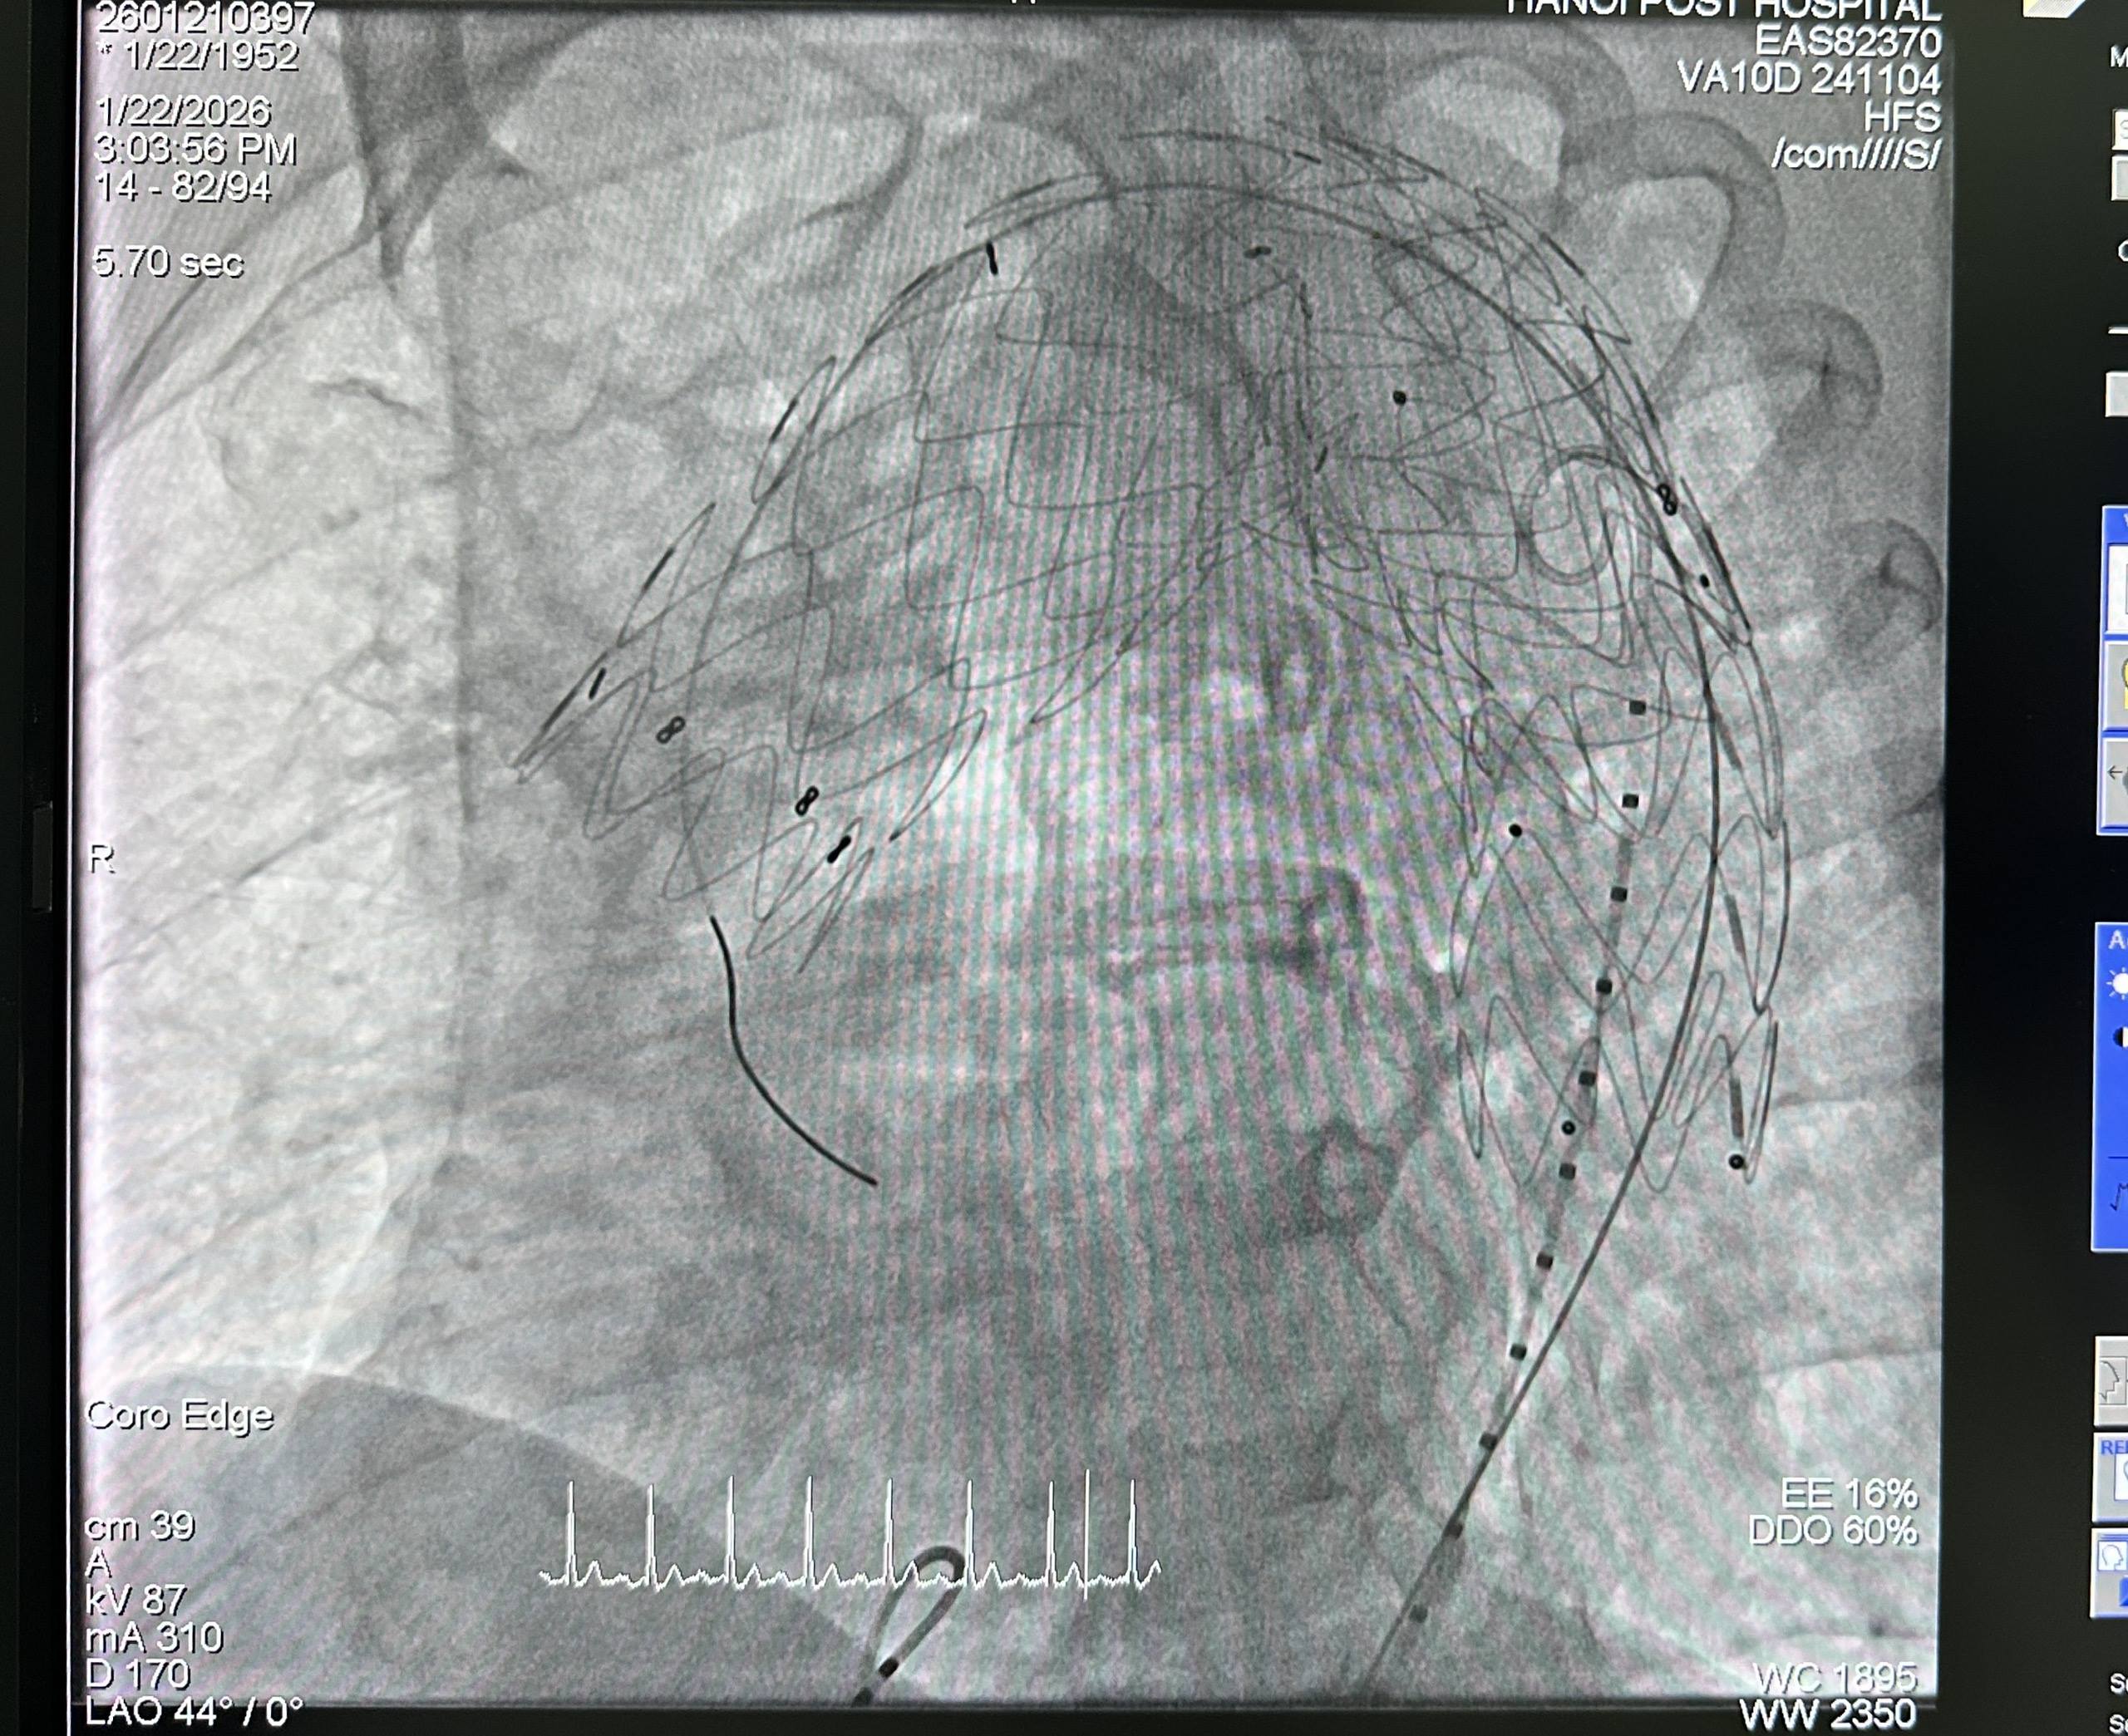

Sau hội chẩn chuyên môn và đánh giá toàn diện bệnh lý nền, thể trạng người bệnh cũng như nguy cơ phẫu thuật, ê-kíp thống nhất lựa chọn phương pháp đặt stent graft nội mạch. Phương pháp này hạn chế xâm lấn, thường không cần gây mê toàn thân, giúp giảm nguy cơ biến chứng và đặc biệt phù hợp với người bệnh cao tuổi có nhiều bệnh lý mạn tính kèm theo. Trong quá trình can thiệp, dưới hướng dẫn hình ảnh DSA, ê-kíp định vị chính xác vị trí túi phình và triển khai stent graft an toàn. Stent graft che phủ hoàn toàn túi phình, tái lập dòng chảy qua động mạch chủ, qua đó phòng ngừa nguy cơ vỡ phình—một biến chứng có thể đe doạ tính mạng. Toàn bộ thủ thuật diễn ra thuận lợi; người bệnh tỉnh táo, các chỉ số sinh tồn được theo dõi liên tục bằng hệ thống monitoring.